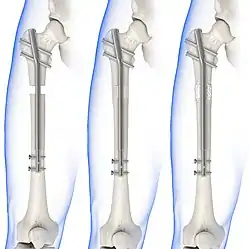

Treatment can be achieved by either non-operative (or conservative) or operative means. The main operative treatments for a Maisonneuve fracture are open-reduction surgery and closed-reduction surgery, both of which usually preceding internal fixation of the injury. These procedures are known as Open Reduction Internal Fixation (ORIF) and Closed Reduction Internal Fixation (CRIF).[6][13]

Internal fixators

Syndesmotic screws are the main, internal fixators used in surgeries for a Maisonneuve fracture. Two main types of syndesmotic screws are used: trans-syndesmotic screws (positioned at the level of the syndesmosis) and supra-syndesmotic screws (positioned above the syndesmosis).[15]

Based on several clinical results, syndesmotic screws are recommended to be fixed at least 1 centimetre proximal to the tibiofibular syndesmosis or 4 to 6 centimetres proximal to the tibiotalar joint line.[4][16] Cadaveric analyses, from a comparative study published in Foot & Ankle International in 1997, suggest that screw fixation at 2 centimetres proximal to the tibiotalar joint line is also adequate.[17] Biodegradable implants such as bioabsorbable screws, which do not require postoperative removal, may be used as an alternative to metallic hardware. However, biodegradable implants still limit rotation of the ankle and dorsiflexion of the foot.[4][6][13]